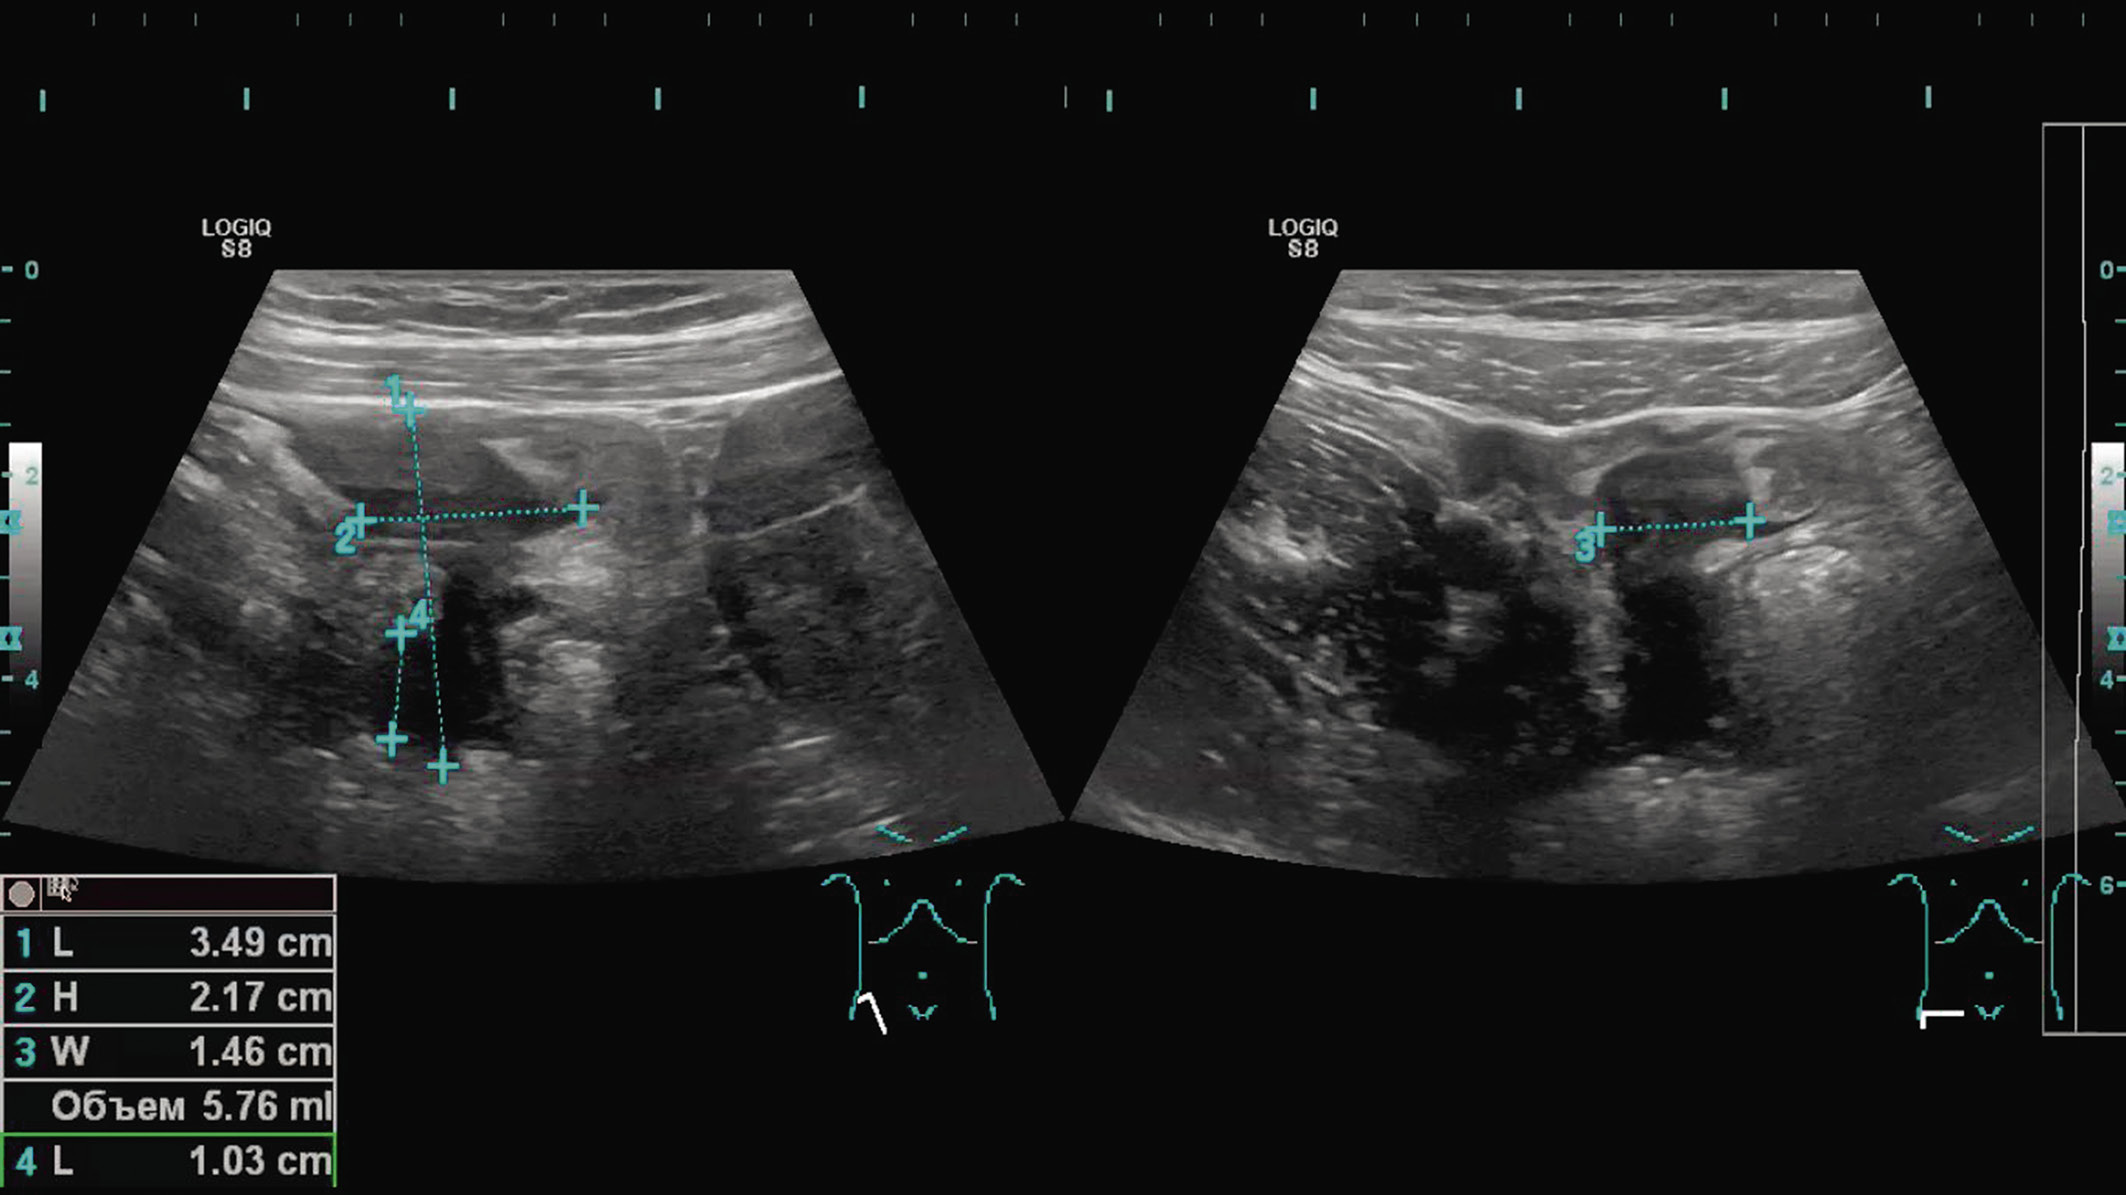

При ультразвуковом исследовании (УЗИ) органов брюшной полости особых изменений не обнаружено. Печень не увеличена, контуры ее четкие, ровные, структура однородная, эхогенность не изменена, сосудистый рисунок не деформирован, внутрипеченочные протоки не расширены. Очаговые изменения не выявлены. Желчный пузырь не увеличен. Его форма обычная, стенка не изменена, содержимое однородное, перивезикальные ткани не изменены. Общий желчный проток не расширен, прослеживается до головки поджелудочной железы, внутрипросветные образования не выявлены. Поджелудочная железа не увеличена. Контуры ее четкие, ровные, структура однородная, эхогенность равна печени. Главный панкреатический проток не расширен. Селезенка не увеличена. Контуры ее четкие, ровные, визуализируемые участки капсулы не изменены. Паренхима однородная. Дополнительные образования в паралиенальном пространстве не определяются. Брюшной отдел аорты не расширен. В проекции выходного отдела желудка патологические изменения не выявлены. В правой подвздошной области илеоцекальный переход не изменен, аппендикулярный отросток достоверно не визуализируется. Проксимальнее по ходу подвздошной кишки, межпетельно на уровне ниже ветвления правой общей подвздошной артерии лоцируется образование размерами 35 × 22 × 15 мм, достигающее стенки таза. Форма его неправильная, структура неоднородная, низкой эхогенности. Аваскулярное образование фиксировано к поверхностно лежащим петлям тонкой кишки, к брюшине не фиксировано (рис. 1).

Рис. 1. Ультразвуковое исследование органов брюшной полости — межпетельное образование по ходу подвздошной кишки / Fig. 1. Ultrasound examination of the abdominal organs — interloop formation along the ileum

Стенки кишки не изменены. Свободная жидкость в брюшной полости не лоцируется. Регионарные лимфоузлы не увеличены. Заключение: эхографические признаки межпетельного образования в правой подвздошной области (очаг наружного эндометриоза?, карциноид?).